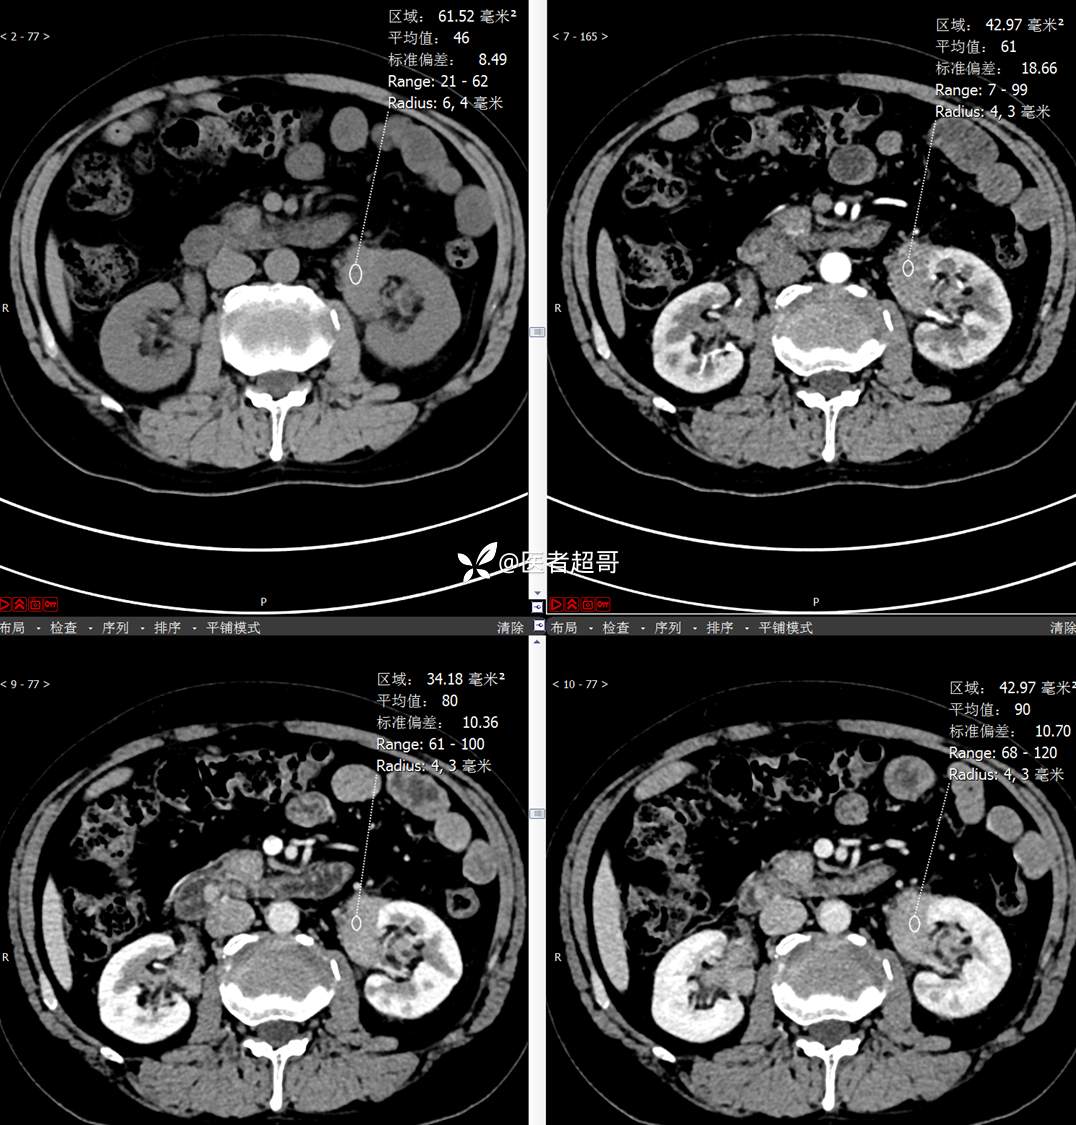

【影诊笔记772】腹痛就诊,发现肾脏病变,CT、MRI齐全,请高诊!

男,63岁 0200825 01

主 诉:间断腹痛15天

现病史:患者15天前无明显原因及诱因出现腹部疼痛不适,呈间断性钝痛,右下腹为著,无尿频、尿急、尿不尽,无发热、寒战,无腹胀。于市中心卫生院住院治疗,超声示:胰头低回声包块,胆系扩张,左肾囊肿,胆囊壁毛糙,胆囊内胆汁淤积。患者为求进一步诊治,遂以“肾盂肿瘤”收入院,患者自发病以来,神志清,精神可,饮食睡眠可,大便无明显异常,近期体重无明显增减。

既往史:既往体健